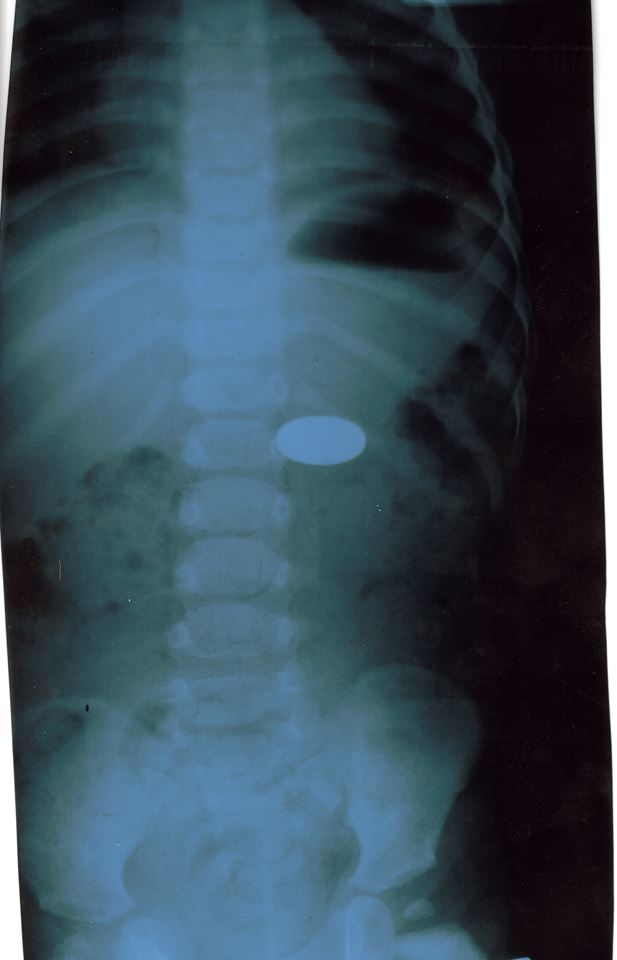

O fetiță în vârstă de 2 ani și 6 luni, din municipiul Chișinău, a fost transportată de urgență la Institutul Mamei și Copilului, după ce a înghițit o monedă de un leu. Aceasta a fost internată în Secția Endoscopie a spitalului.

În urma unei intervenții, medicii au putut extrage cu succes corpul străin care se afla în tractul digestiv al pacientei. Micuța a fost deja externată la domiciliu, fără ca starea ei de sănătate să fie pusă în pericol.

De la începutul anului 2019 au fost efectuate deja 16 intervenții de extragere a obiectelor străine din tractul digestiv superior al celor mici. În șapte din cazuri a fost vorba de înghițirea unor monede.